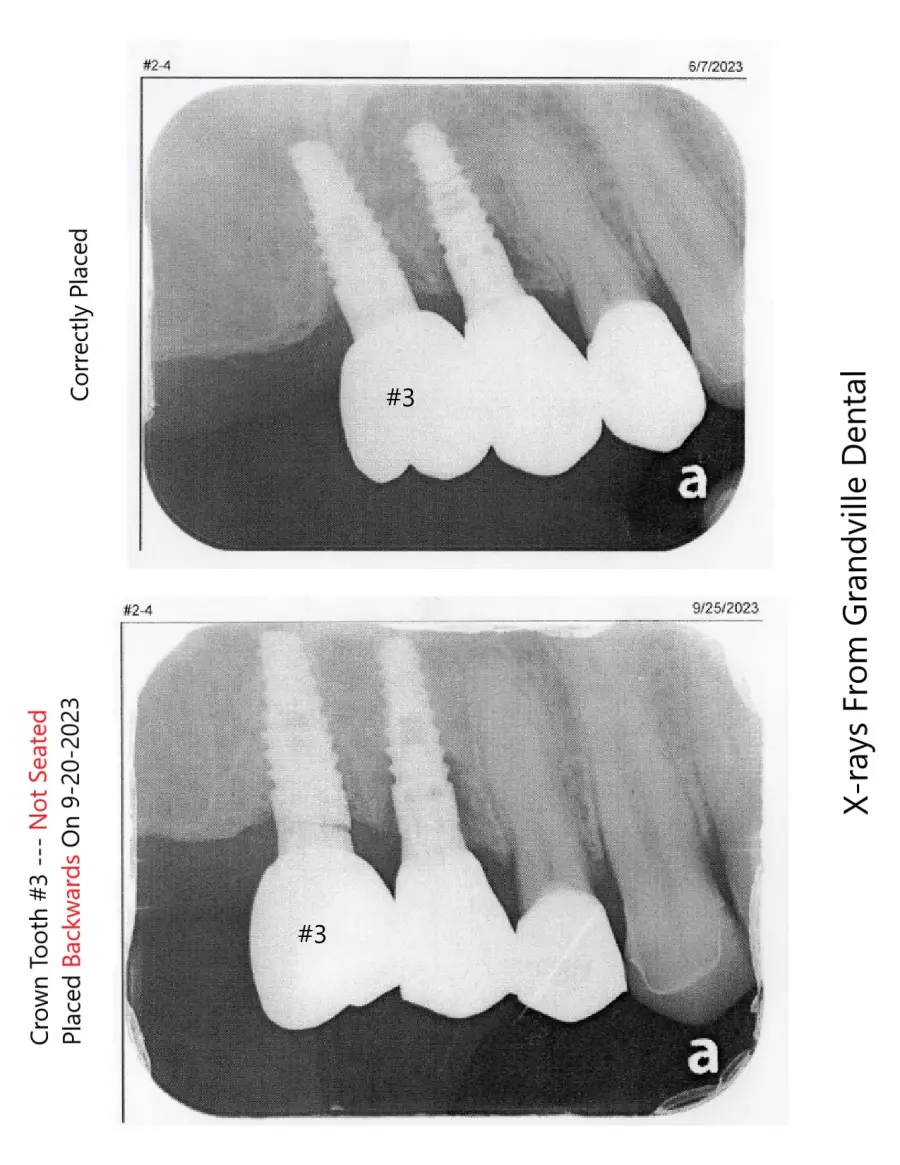

WMDDS please go look at photo #120 - This is a huge oversight error.

Dr. Rebecca Vanderbaan & Dr. Larissa Bishop The Past President Of The WMDDS Placed A Dental Crown Tooth #3 Backwards And Wrecked My Restoration. A Bridge became loose, A veneer chipped, A crown fell off, another crown became loose, 8 teeth are not touching each other and I have bone loss on several new implants likely caused from this.

How did a implant supported crown get placed 180 degrees backwards then get missed then several adjustments to the adjacent teeth were made on four different separate occasions until there was no bite on 8 teeth. Permanent adjustments were made to teeth #5, #6, #7, #26, #27 and #28 all based on a crown tooth number 3 being placed backwards and then let me go with a non-functioning bite.

The WMDDS should be looking hard at Photo #120 and look close at tooth #3 then compare it to the model the way the tooth was supposta be placed and you will see tooth #3 was placed 180 degrees backwards and not known for a whole year biting my tongue and cheek everyday over 300 times and sometimes to the point of bleeding and I told the dentist my tooth #3 is biting my tongue and check every single day but everyone ignored it and let me keep biting myself. Photo #120 is the photo that the dental association was weirdly missing. The WMDDS should go back and actually look at this case and see how the clinical exam was unfair, biased and no x-rays or bitechecks were even taken during there clinical exam.

It seems to be money is what matters here and I cannot simply get my teeth fixed because biased behaviors exist and the doctors only seem to care about the money. I tried to update the dental association about this backwards crown tooth #3 before the state dental board met and made a decision on this case but was told it's too late for the board to receive new information for review. There has been a major oversight error and this patient should be entitled to enough reimbursement from their member to fix 4 crowns so his teeth will simply function weather reimbursed or paid to the new dentist to get his teeth functioning it's not about the money it's about getting an even, working and functioning bite that's actually within standard care.